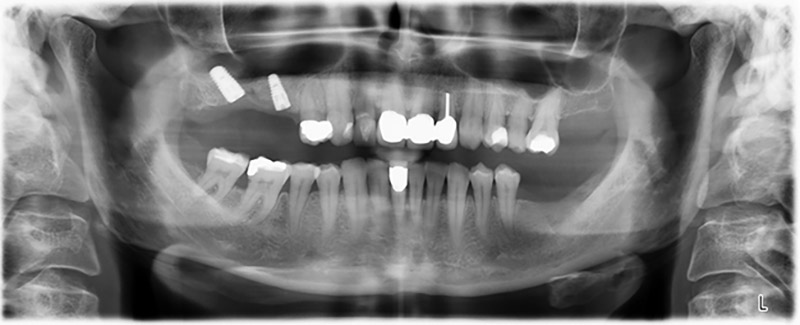

The 59-year-old patient presented with an advanced case of periodontitis, describing an unpleasant feeling and poor taste from the first quadrant in a distal direction. The clinical examination revealed generally enlarged periodontal pockets and very advanced bone atrophy in regions 16 and 14. The radiology confirmed the findings (Fig. 1). Teeth 16 and 14 could not be retained.

About six months after teeth 16 and 14 were extracted, a digital volume tomography (DVT, Planmeca) examination was performed for planning and risk minimization purposes. It clearly showed that the bone had not regenerated to the desired volume (Fig. 2 to 7).

To restrict the augmentation to region 14, and in consultation with the patient, it was planned that implant 16 would be placed, inclined, in the dorso-cranial direction (Fig. 8).